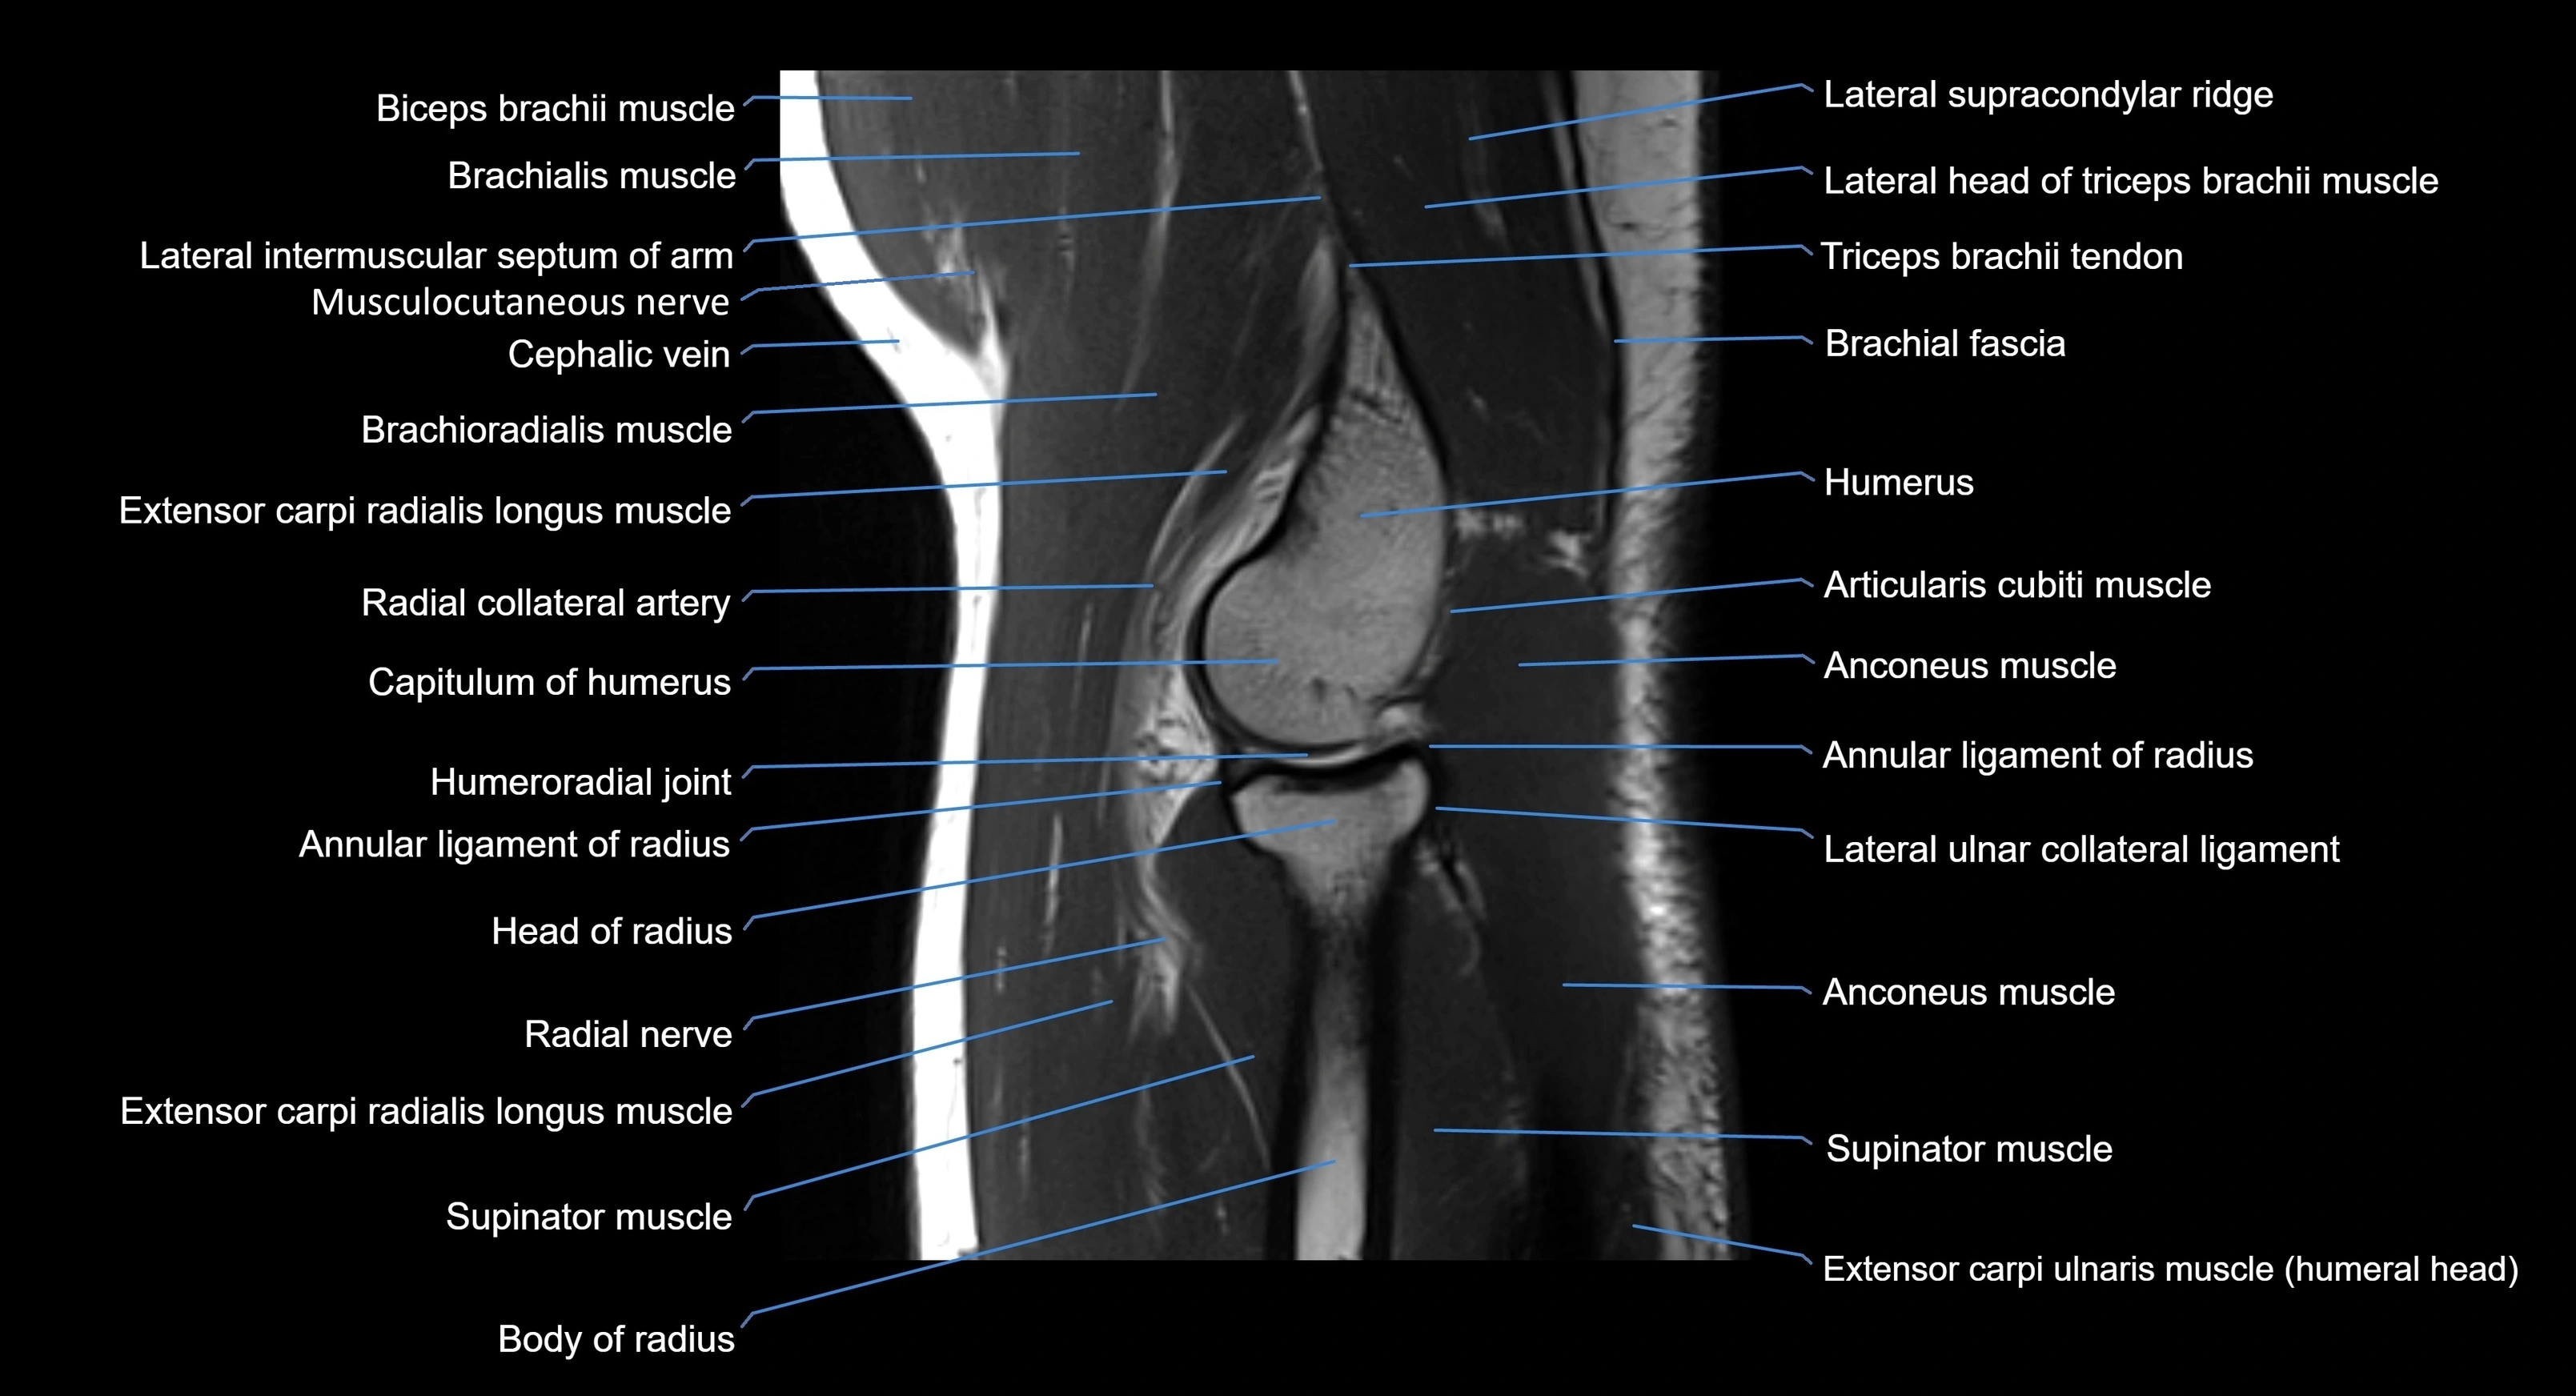

MRI image

image